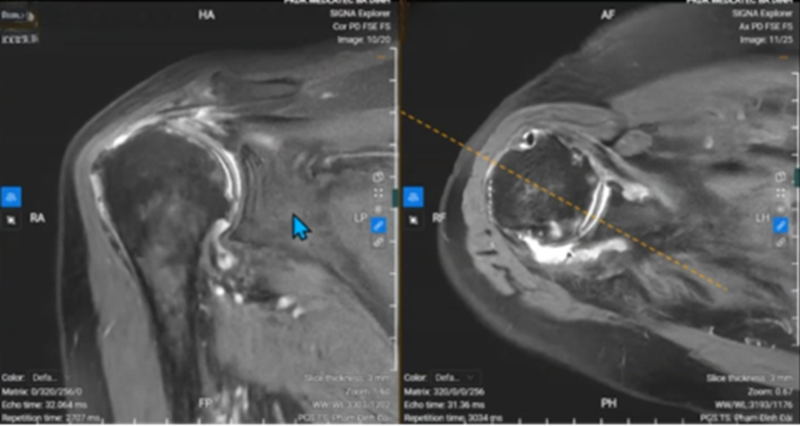

Để chẩn đoán bệnh viêm khớp dạng thấp, người ta thường dựa vào triệu chứng lâm sàng kết hợp với chẩn đoán hình ảnh và kết quả xét nghiệm của bệnh nhân.

Các xét nghiệm thăm dò bệnh gồm có: xét nghiệm yếu tố dạng thấp - RF, xét nghiệm anti - CCP, xét nghiệm ESR (tốc độ máu lắng), chụp X - quang,… Trong đó, xét nghiệm yếu tố dạng thấp và xét nghiệm anti - CCP là hai xét nghiệm quan trọng và chính xác nhất trong chẩn đoán bệnh.